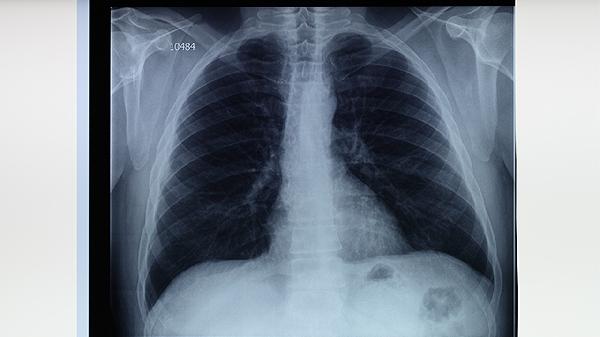

胸部X線或CT檢查可發(fā)現(xiàn)肺結(jié)核特征性改變,如上肺野浸潤(rùn)影、空洞形成或纖維鈣化灶。影像學(xué)能評(píng)估病變范圍與嚴(yán)重程度,但對(duì)不典型病例鑒別診斷價(jià)值有限。活動(dòng)性肺結(jié)核常見多形態(tài)混合病灶,需與肺炎、肺癌等疾病鑒別。兒童肺結(jié)核可能僅表現(xiàn)為肺門淋巴結(jié)腫大,需特別注意。